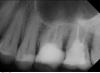

ОльгаВМ Опубликовано 5 ноября, 2012 Поделиться Опубликовано 5 ноября, 2012 Уважаемые доктора,интересует ваше независимое мнение о состоянии пломбировки корней.Я бы хотела поставить коронки на 15, 16 и 26, 27 (верхняя челюсть). Нужно ли перелечивать каналы ? Есть ли там воспаление? Ссылка на комментарий

DokDent Опубликовано 5 ноября, 2012 Поделиться Опубликовано 5 ноября, 2012 Надо перелечивать каналы в этих зубах,менять пломбы в 1.8;1.4 и лечить 1.7 Ссылка на комментарий